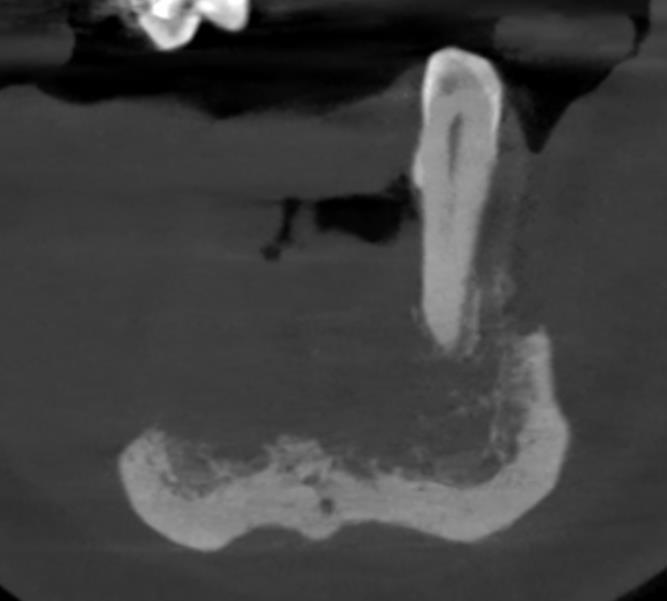

W okolicy okołospojeniowej i przednich odcinkach trzonów żuchwy widoczna rozległa, słabo odgraniczona zmiana osteolityczna o orientacyjnych wymiarach 36x12x16 mm, o szerokiej strefie przejściowej i permeacyjnym typie naciekania, rozciągająca się w głównej mierze od okolicy zębodołu 33 do okolicy 45 (ząb całkowicie poza kością). Na poziomie największego ubytku w okolicy 32-42 widoczne jedynie częściowo zachowane blaszki zbite językowa i podstawy żuchwy.

Poza tym w obrębie żuchwy widoczne obszary rozrzedzenia struktury kostnej wtórne prawdopodobnie do zaniku kostnego i zmiany osteolityczne okołowierzchołkowe zębów oraz zmiany zapalne przyzębia brzeżnego, co utrudnia rozgraniczenie zasięgu nacieku. Naciek rozciąga się prawdopodobnie wzdłuż części zębodołowej trzonu żuchwy niemal od zębodołu 38 do okolicy zębodołu 46 z częściowym objęciem korzeni zębów 36-34 i całkowitym korzenia zęba 45.

Korzeń resztkowy zęba 35. Korzeń objęty zmianą zapalną śr. ok. 10 mm częściowo wyodrębniającą się z agresywnego nacieku.

Korzeń zęba 34 w całości poza kością objęty zmianami naciekowymi i zapalnymi przyzębia brzeżnego.